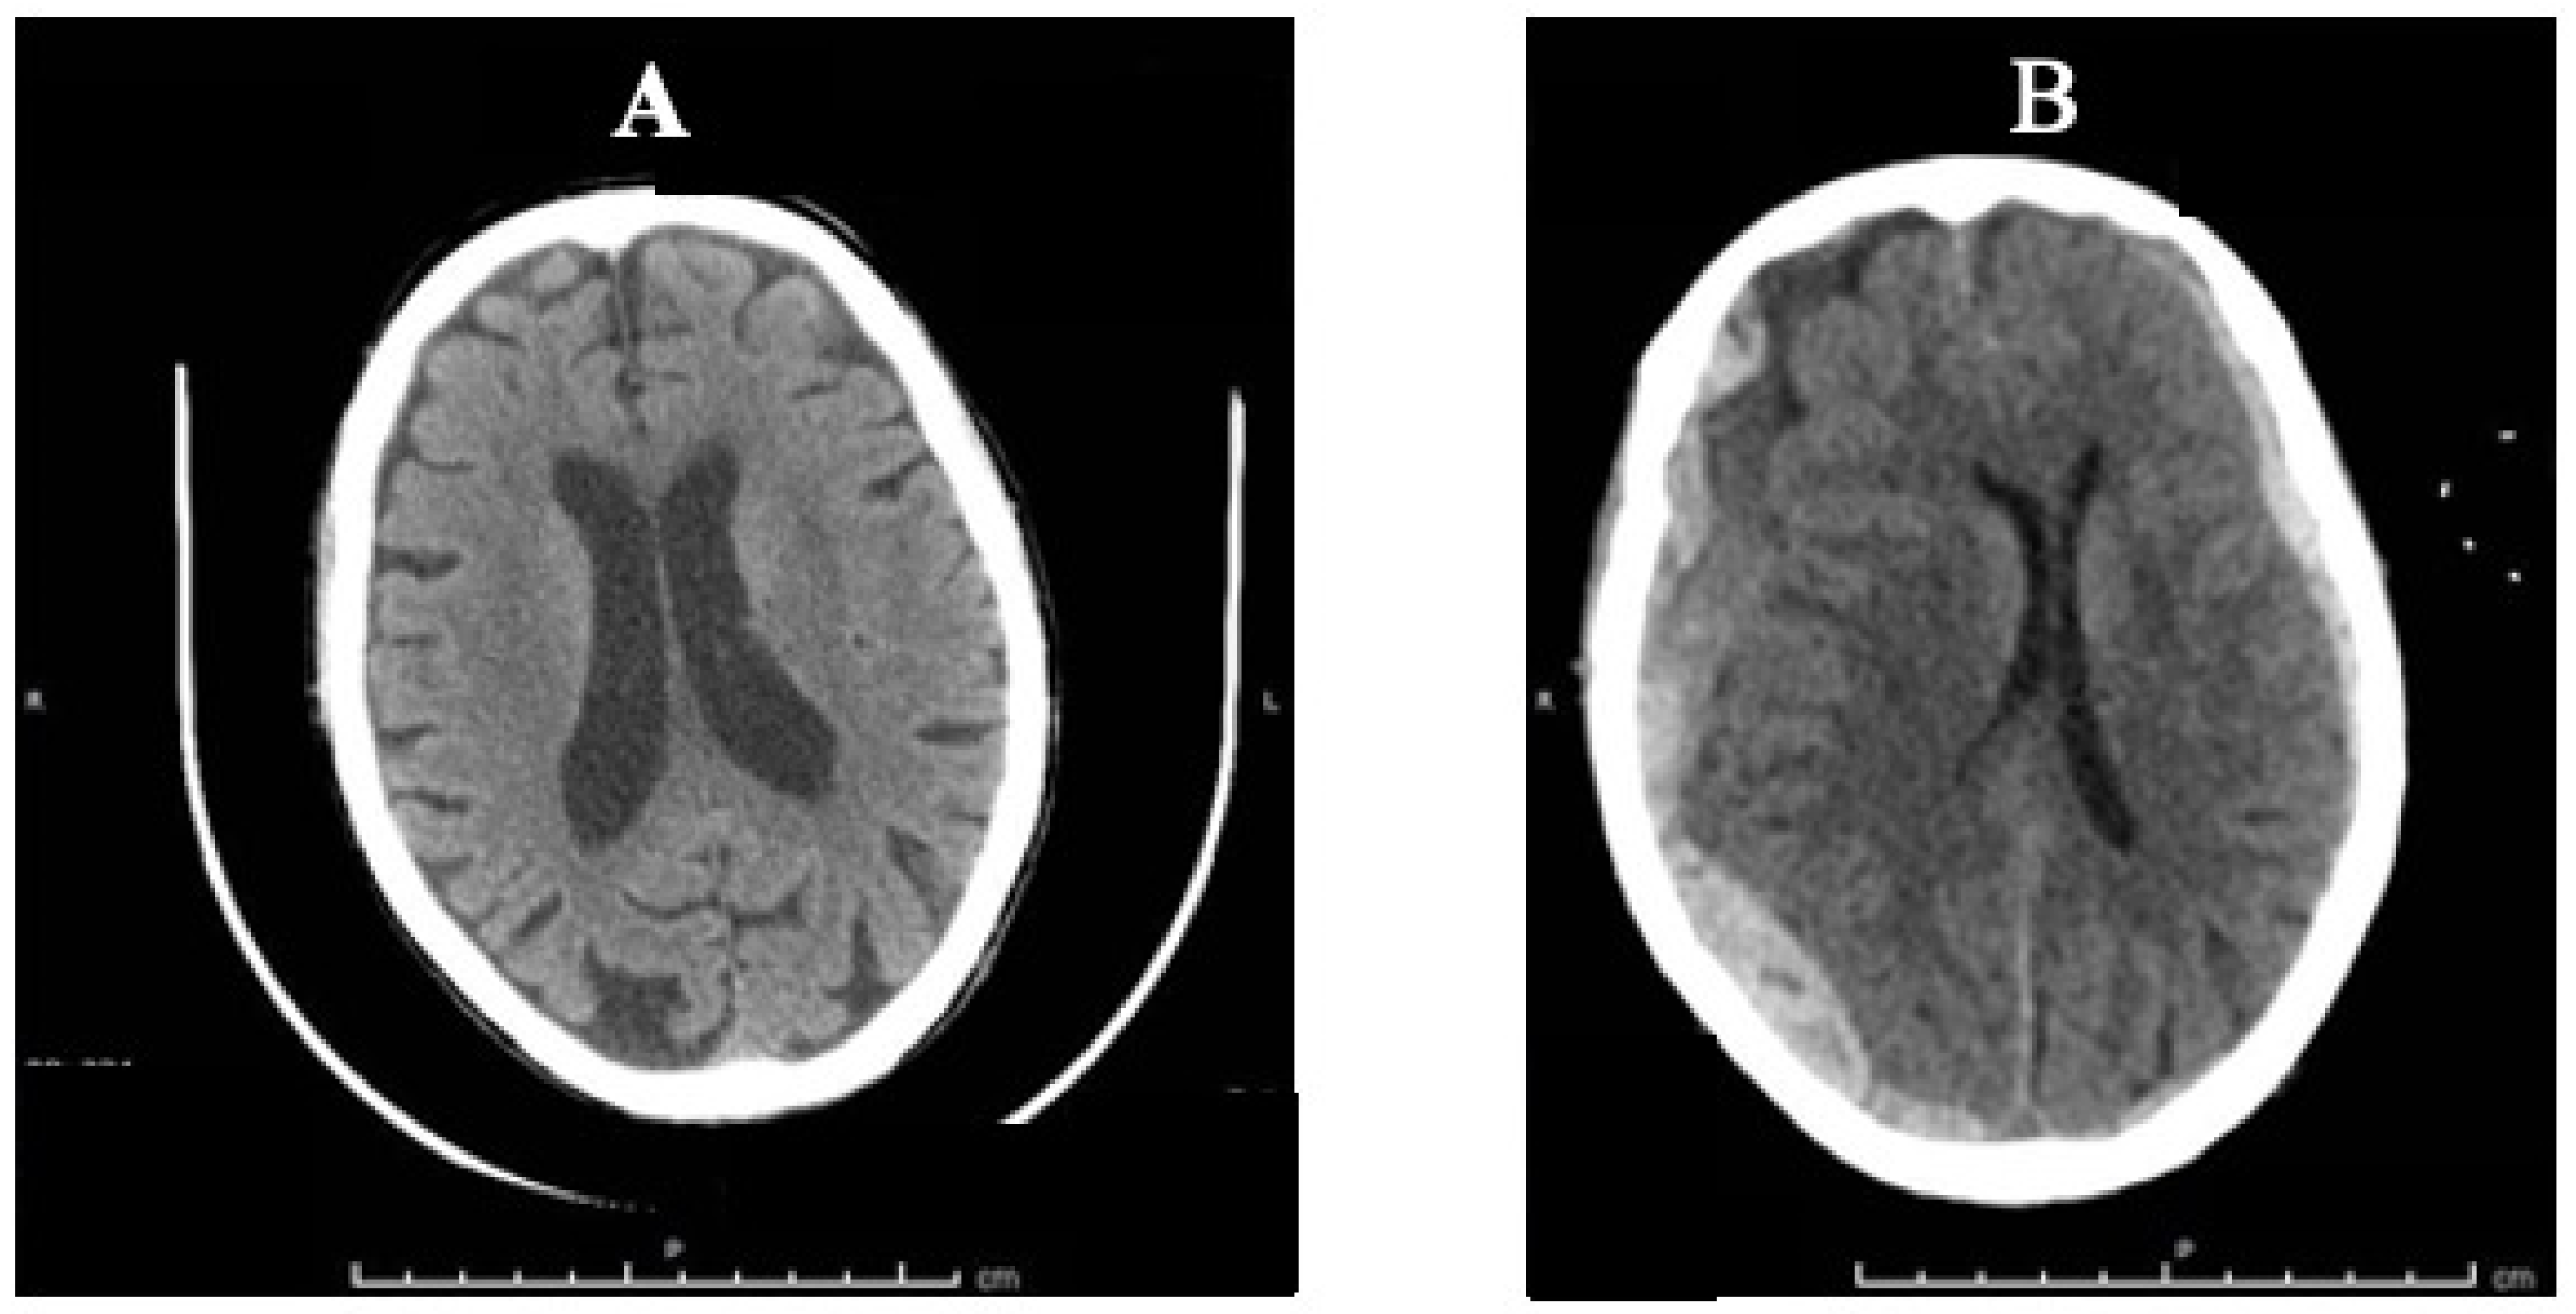

A 82-year-old Caucasian woman living with her husband and a caretaker was found at home unconscious and unresponsive. The caretaker said the old woman had been put to bed about two and a half hours before. Soon after the reported finding, the woman was transported to a third level hospital’s Emergency Department. A medical history of widespread cortical atrophy, progressive cognitive impairment, depression, hypertension, hypercholesterolemia, osteoporosis, megaloblastic anemia and mild renal insufficiency was reported. The therapy adopted before the hospitalization was represented by antidepressants such as trazodone, medications for treating high blood pressure such as anti-calcium channel blockers (amlodipine) and platelet aggregation inhibitors such as ticlopidine. A cranioencephalic CT-scan showed a right parieto-temporal subdural hematoma (SDH), 21 mm thick, compressing the right lateral ventricle and third ventricle, causing a midline shift of about 9 mm. Additional findings were represented by a left temporo-occipital SDH, 8 mm thick, right temporo-basal intraparenchymal hemorrhages and blood in the fourth ventricle (Figure 1A). No fractures or other traumatic injuries of the internal organs were found in the thorax or abdomen. There was no indication of neurosurgical treatment. It is worth mentioning that a cranioencephalic CT-scan was performed just two months before the event. This previous imaging exam showed findings consistent with chronic ischemic encephalopathy and enlargement of intracranial cerebrospinal fluid spaces, but no other pathologic abnormalities were reported (Figure 1B).

Figure 1.

CT-scan comparison: (A) Two-month-old CT scan with signs of chronic ischemic encephalopathy and enlargement of intracranial cerebrospinal fluid spaces; (B) CT-scan made in the hospital showing bilateral SDH.

As above mentioned, rapid deceleration/ acceleration of the head or rapid changes in rotation and angular forces can easily occur during a violent shaking, resulting in tears of the bridging veins that drain blood into the dural venous sinuses [30,31] in adults too—especially if elderly. The intracranial changes that occur with aging can also be considered favorable factors for intracranial bleeding and the formation of SDH, even after mild or minor head trauma, with or without impact [32]. These age-related changes are mostly represented by increased adherence of the dura to the skull, cerebrovascular atherosclerosis increasing the bridging vein fragility, and progressive brain atrophy extending the distance between the cortex and the overlying coverings. This is the reason why the minimum force required to produce serious intracranial consequences is still not known. It has been reported that about 30% of all cases of SDH involve isolated SDH without associated skull fracture, skin wounds and cortical or intracranial hemorrhages [34,42]. The absence of external signs of scalp lacerations, skull fractures, or soft tissue swelling in many cases of SDH probably results in the role of the impact injury being underestimated. In our case, there were signs suspicious of multiple impact injuries to the head, as represented by the multiple small bruises on the vertex and the face (mostly at the left side), associated with a frontoparietal hematoma and a bilateral subacute SDH. The patterned polychromatic bruises distributed on the dorsal and lateral surfaces of the upper extremities and lateral chest on both sides were instead consistent with forceful grasping/gripping or repeated blows. Since SDH can be caused by rapid acceleration/rotation in absence of impact or by mild/minor blows, it is such a mechanism that probably occurred in our case. A number of underlying conditions may predispose one to SDH, including coagulopathies and anticoagulant therapy. In our case, the use of an antiplatelet drug aggregation inhibitor (ticlopidine) was also an additional factor increasing the risk of intracranial bleeding. In fact, the iatrogenic etiology of SDH was taken into account but considered as only a contributing factor and not a primary cause of death. Ticlopidine is an adenosine diphosphate (ADP) receptor inhibitor that interferes with platelet membrane function and platelet–platelet interactions, reducing the risk of thrombotic strokes. As ticlopidine prolongs bleeding time, its use is not indicated in cases of bleeding diathesis, hematological and sever liver diseases or in association with drugs that increase the risk of bleeding such as non-steroidal anti-inflammatory drugs (NSAIDs) or anticoagulant agents. Apart from ecchymosis, epistaxis, hematuria and conjunctival hemorrhage, among the adverse reactions, gastrointestinal rather than intracerebral bleeding is also described [43,44]. Neither contraindications nor overdosage were observed in the present case and the victim had been properly taking ticlopidine for many years without any adverse effect. Spontaneous SDH exists, although its pathogenesis has been questioned [34,45,46]. Most spontaneous SDHs are arterial in origin, caused by hypertensive peaks in blood pressure or from the rupture of a cerebral arterial aneurysm or even related to hematological or hepatic coagulation disorders. However, in the present case, no elements suggestive of a non-traumatic cause of SDH were found at autopsy, including aneurysm or arterial–venous malformation rupture, cocaine abuse, metastatic cancer or Moyamoya disease [45,47,48]. The results of the CT-scan performed two months before the fatal event ruled out intracranial hemorrhages and other main pathological abnormalities, only detecting signs of age-related intracranial changes, as represented by cerebral atrophy with enlargement of the intracranial cerebrospinal fluid spaces and chronic ischemic encephalopathy (Figure 1A,B). An additional point worthy of consideration is the following: SDHs are often seen in falls. Unfortunately, age is one of the key risk factors for falls and older people have the highest risk of death or serious injury, with devastating consequences arising from a fall. It is estimated that more than one-third of persons 65 years of age or older fall each year. Falls represent a public health problem since they are the second leading cause of unintentional injury deaths worldwide [4]. However, in our case, the association of bilateral SDH with multiple polychromatic bruises on the face, the chest and the upper limbs were more consistent with repeated physical abuses than a single accidental fall. This assessment was central to the subsequent judicial process; following investigations proved that physical abuse occurred.